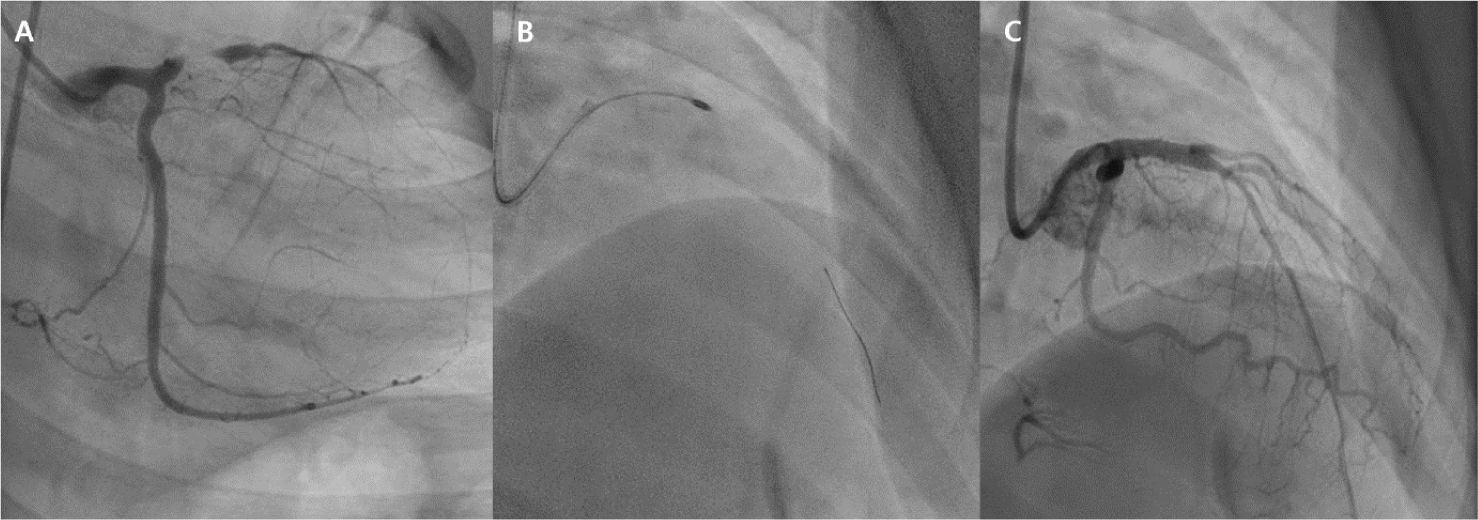

From 1998 to 2023, we performed 13 coronary revascularization procedures in 11 patients at our institution. Demographic and angiographic characteristics of patients with aneurysms are summarized in Table 1. The majority were male (n = 8, 72%), and the median age at KD onset was 3.7 years (range, 1.7–6.0 years). Aneurysms involved various coronary segments, most commonly the RCA and the left anterior descending artery (LAD). Giant aneurysms, defined as ≥ 8 mm in diameter, were identified in 7 of the 11 patients (63%). Most patients received dual antiplatelet therapy or a combination of warfarin and aspirin. Procedural data are summarized in Table 2. The median age at the time of the procedure was 10.1 years (range: 3.9–40.6 years). The treated coronary arteries included the RCA in 9 cases, followed by the LAD in 4 cases, the left circumflex artery in 1 case, and the bypass graft anastomosis site in 1 case. Six patients underwent PTCA, including one case involving stenosis at the anastomosis site of a bypass graft. The median follow-up duration after the PCI was 2.9 years (range, 0.7–13.7 years). All PTCA procedures were immediately successful. Although no neo-aneurysm formation was identified on follow-up imaging, interpretation is limited by the short follow-up duration and the lack of imaging data in a substantial proportion of patients (4 of 11). One patient (17%) developed a dissection post-PTCA. Another patient (17%) experienced restenosis of the RCA six months after initial PTCA, requiring repeat PTCA and DES implantation. The restenosis rate after PTCA (1 of 6, 17%) was comparable to that reported in a previous study (24%) [18]. Four patients underwent DES implantation initially—three following PTCA and one PTCRA. One patient (25%) developed total occlusion of the RCA eight months after stent implantation and underwent successful PTCRA. In total, three patients underwent PTCRA, all with immediate procedural success. Two deaths (18%) were recorded during the follow-up period: one unrelated to coronary artery disease and the other in a patient with severe ventricular dysfunction.